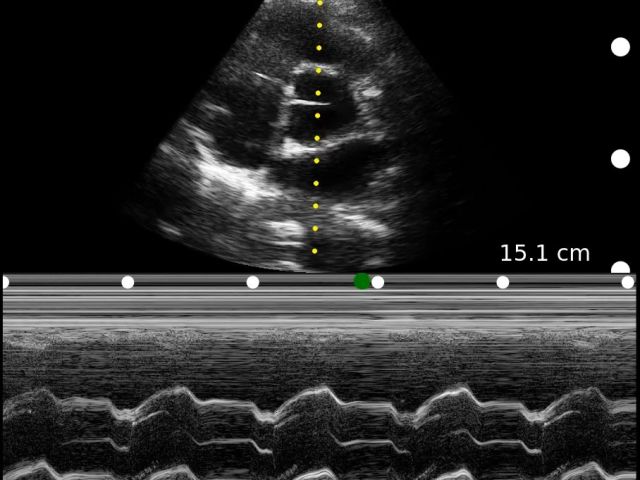

Medical professionals love the high portability, easy of use, and high-definition imaging of the Clarius C3 HD3 multipurpose scanner for full body imaging up to 40 cm. It’s the leading choice for medical professionals looking for premium imaging in an affordable scanner. Artificial intelligence, specialized presets and customizable workflows automatically optimize imaging for a seamless experience.

Applications: Abdominal, Cardiac, Lung, OB/GYN, Superficial

Clinical Images